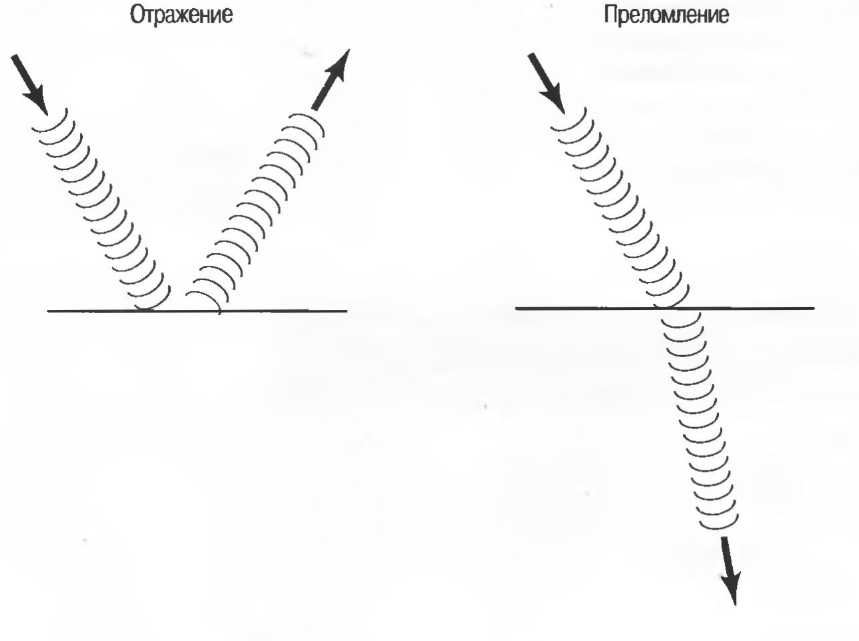

Отражение |

Изменение направления ультразвуковой волны на границе раздела сред, при этом ультразвуковой луч не проходит через вторую среду. Также известно как «эхо». См. также Зеркальный отражатель. |

Ультразвук может отражаться или преломляться на границе двух различных типов тканей: отражение означает возвращение сигнала назад, а преломление — изменение направления; при этом необязательно имеет место отражение.

Часть излучаемых (1) волн отражается (2), при этом угол отражения равен углу падения. Другая часть волн (3) проходит через поверхность и преломляется, распространяясь далее под углом, отличным от угла падения. Чем более выражена разность акустического сопротивления двух сред, тем больше отражается ультразвук. Чем больше отношение скоростей распространения, тем больше преломление. Для практики важно знать, что при нулевом значении угла падения ультразвук падает на поверхность перпендикулярно.